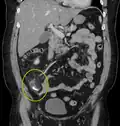

| A fecalith marked by the arrow which has resulted in acute appendicitis. | |

A fecalith is a stone made of feces. It is a hardening of feces into lumps of varying size and may occur anywhere in the intestinal tract but is typically found in the colon. It is also called appendicolith when it occurs in the appendix and is sometimes concurrent with appendicitis.[1] They can also obstruct diverticula. It can form secondary to fecal impaction. A fecaloma is a more severe form of fecal impaction, and a hardened fecaloma may be considered a giant fecalith. The term is from the Greek líthos=stone.[2]

A small fecalith is one cause of both appendicitis and acute diverticulitis.